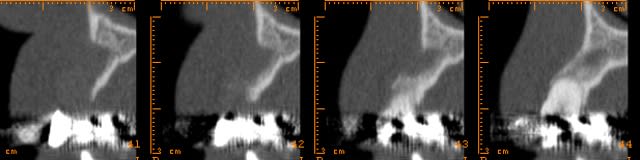

le protocole de Khoury basé sur ses parfaites connaissances du phénomène de cicatrisation permet d'obtenir des greffons de super qualité au moment de la mise en place des implants.

Screenshot015 copie ryteqf - Eugenol

Img 4922 dw6gpg - Eugenol

Img 4924 qsttsv - Eugenol